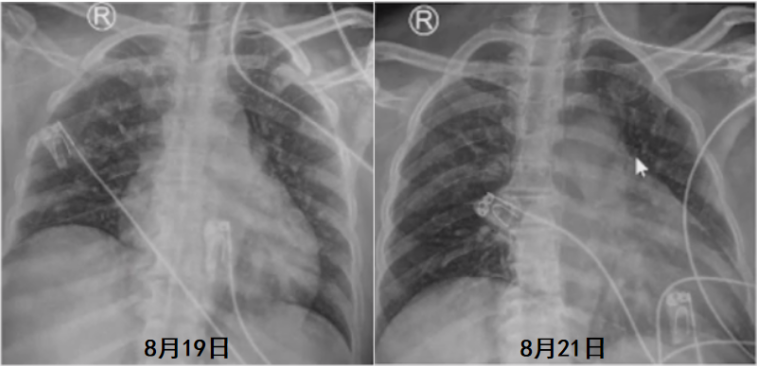

经过上述治疗,患者炎症指标有所下降(表5),胸部X线片较前好转(图7)。

8月19日复查血气分析(呼吸机辅助呼吸,SPONT模式,PSV 18 cmH2O,PEEP 8 cmH2O,氧浓度35%):pH 7.520,PaCO2 56.0 mmHg,PaO2 144.0 mmHg,SaO2 99%。SBT通过,复查支气管镜见气道内少许分泌物,黏膜光滑无肿胀,于8月19日脱机拔管,序贯无创呼吸机辅助呼吸。气管导管尖端培养、灌洗液培养(8月19日送检)均为肺炎克雷伯杆菌;血培养(8月16日送检)为白色念珠菌。血NGS回报金黄色葡萄球菌(序列数3),覆盖度0.01%。继续延用替加环素+多黏菌素B+卡泊芬净的治疗方案。患者8月19日拔管后仍出现反复发热,考虑仍与感染有关。然而,从8月21日胸部X线片可见肺部病变有所好转(图8)。8月22日胸部CT可见两侧胸腔积液明显吸收,双肺实变、渗出灶较前明显好转(图9)。考虑患者发热的原因可能并非肺部感染。8月23日查体见患者背部、腹股沟区、左下肢点片状红疹。考虑可能为药物热所致,遂停用多黏菌素B、替加环素,改为哌拉西林他唑巴坦4.5 g ivgtt q8h抗感染治疗,继续卡泊芬净抗真菌治疗。调整治疗方案后患者最高体温下降,但仍有发热。为了排查感染问题,8月26日拔除PICC管,之后2~3天,患者体温逐渐恢复正常。因此考虑患者可能合并血流感染。之后患者一般情况好转,8月27日复查胸部X线片提示病情进一步好转(图10)。8月29日转入普通病房,后一直未再发热,9月13日出院。